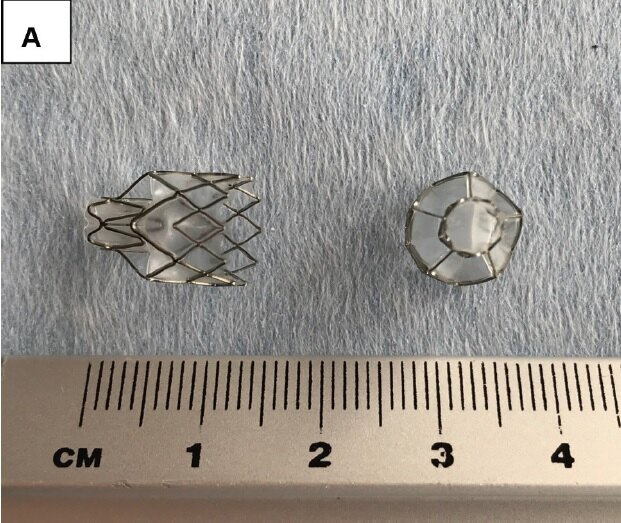

目前全球有4种支气管活瓣,比较常用的是Pulmonx公司生产的Zephyr endobronchial valve (EBV)活瓣,Olympus公司生产的Spiration valve system (SVS,以前叫Intrabronchial Valve, IBV)活瓣。EBV活瓣是一种在镍钛合金骨架上覆盖硅酮膜形成一个鸭嘴样的结构,IBV活瓣是是在伞状镍钛合金骨架上覆盖一层多聚合物膜。由于EBV活瓣在国内更加常用,本次就以EBV活瓣为例介绍支气管活瓣肺减容。目前EBV活瓣有两种规格,Zephyr 4.0(张开后直径4.0 – 7.0 mm)、Zephyr 5.5 (张开后直径5.5 – 8.5 mm)。

图A. EBV活瓣

图B. EBV活瓣放置于支气管亚段开口